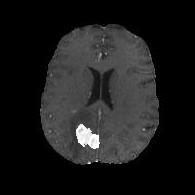

(a) (b) (c) (d)

Boundary Stream:

Fig. 2 demonstrates the output of each of the attention layers in our dedicated boundary stream. In essence, each attention layer progressively localizes the tumor and refines the boundaries. The first attention layer has learned rough estimate of the boundaries around the tumor and localized it, whereas the second and third layers have learned more fine-grained details of the edges and boundaries, refining the localization. Moreover, since our architecture leverages a dilated spatial pyramid pooling to merge the learned feature maps of the regular segmentation stream and the boundary stream, multiscale regional and boundary information have been preserved and fused properly, which has enabled our network to capture the small structural details of the tumor.

(a) (b) (c) (d) (e)

Comparison to Competing Methods:

We have compared the performance of our model against the most popular deep learning-based semantic segmentation networks, U-Net [9] and V-Net [7] (Fig. 3). Our model outperforms both by a considerable margin in all evaluation metrics. In particular, U-Net performs poorly in most cases due to the high false positive of its segmentation predictions, as well as the imprecision of its boundaries. The powerful residual block in the V-Net architecture seems to alleviate these issues to some extent, but V-Net also fails to produce high-quality boundary predictions. The emphasis of learning useful edge-related information during the training of our network appears to effectively regularize the network such that boundary accuracy is improved.